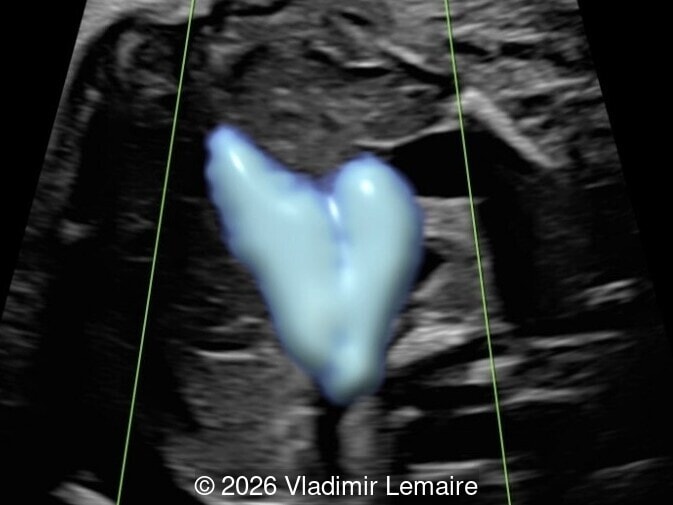

Sagittal 3D glass-body mode demonstrates the arteriovenous fistula between the deep choroidal arteries and the embryonic median prosencephalic vein of Markowski.

Image 3 Sagittal 3D glass-body mode demonstrates the arteriovenous fistula between the deep choroidal arteries and the embryonic median prosencephalic vein of Markowski.